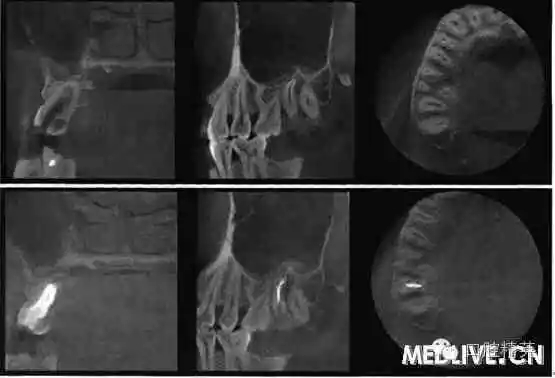

7⊥頜面中央窩見開髓洞型,叩痛(++),無(wú)松動(dòng)。X線片示7⊥牙根融合為一彎曲單根,根管粗大,根尖1/3偏向遠(yuǎn)中,無(wú)充填物,未見髓室底(圖1上)。錐形束C’r檢查示:根管橫斷面僅見一個(gè)根管口略呈啞鈴形,頰舌向管徑粗大,中下1,3存在牙本質(zhì)島,根尖1,3明顯彎曲偏向遠(yuǎn)中,彎曲角度為34.30(圖2上)。

圖1上:初診;下:根管充填后

上:初診:下:根管充填后。

圖2錐形柬CT影像